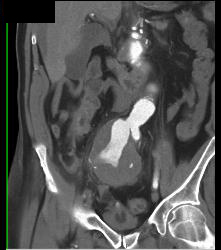

Atherosclerotic Changes in SMA